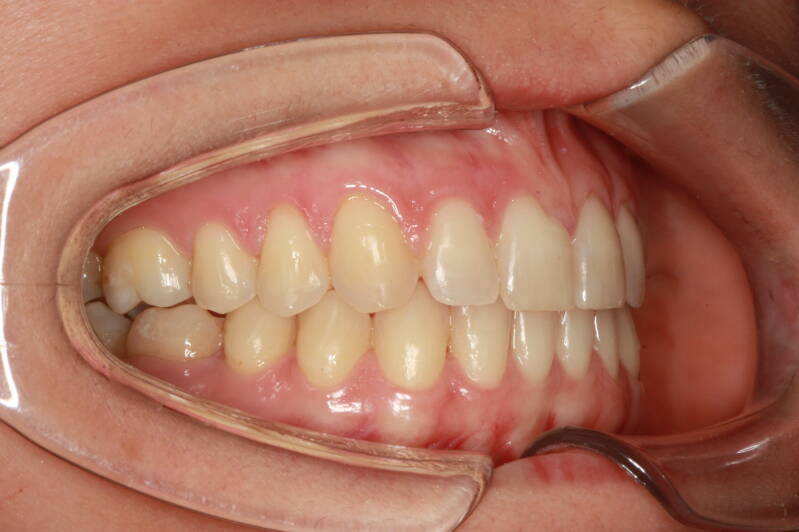

FOTO FINALI DOPO 24 MESI CIRCA DI TERAPA ORTODONTICA FISSA

Abbiamo appena portato a termine questo caso che presentava in arcata superiore il primo premolare di sinistra completamente fuori arcata sovrapposto al secondo premolare ed il canino ruotato.

in arcata inferiore invece abbiamo estratto il secondo molare di sinistra perso per carie deostruente e mesializzato il terzo molare in modo da chiudere lo spazio e non ricorrere all'inserimento di protesi implantare.